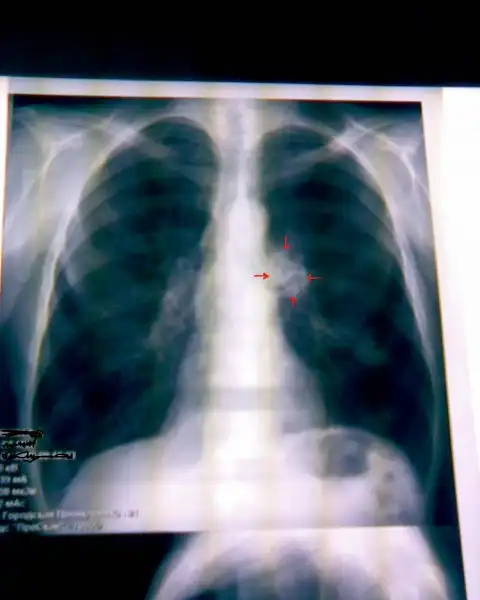

НОРМА: